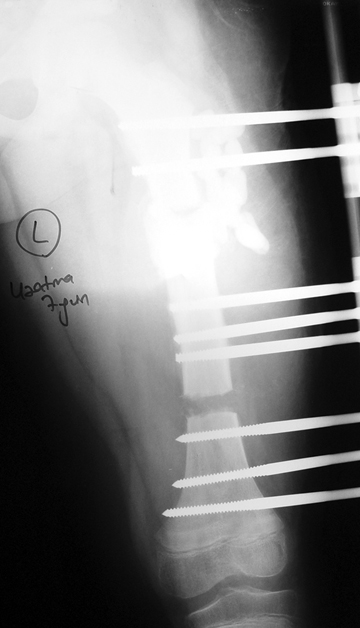

Appropriate radical debridement necessitates excision of all necrotic bone and soft tissues, and frequently causes instability at the involved extremity. The remaining bone and soft tissue defect has to be fixed and reconstructed. The distraction osteogenesis method of Ilizarov is used successfully for achievement of union, correction of the deformity, elimination of limb length inequality and reconstruction of segmental bone defects.

The duration of external fixation (external fixation index) depends on the amount of distraction required, and the extremity is prone to complications during this period. After the distraction phase is completed, the external fixator remains in place during the consolidation phase, which lasts twice as long as the distraction phase; but this period is hardly tolerated. If the external fixator is removed before sufficient consolidation is achieved, fractures, deformity and shortness will be the result. In our department, ‘lenghthening over nail’ method is used in order to decrease the external fixation index and increase patient comfort and activity level. In this method, the intramedullary nail is statically locked after the completion of the distraction phase, and external fixator is removed. The extremity is stabilized by the intramedullary nail during consolidation phase. In this way, complications due to long external fixation index or early removal of the external fixator are avoided.

Case 3